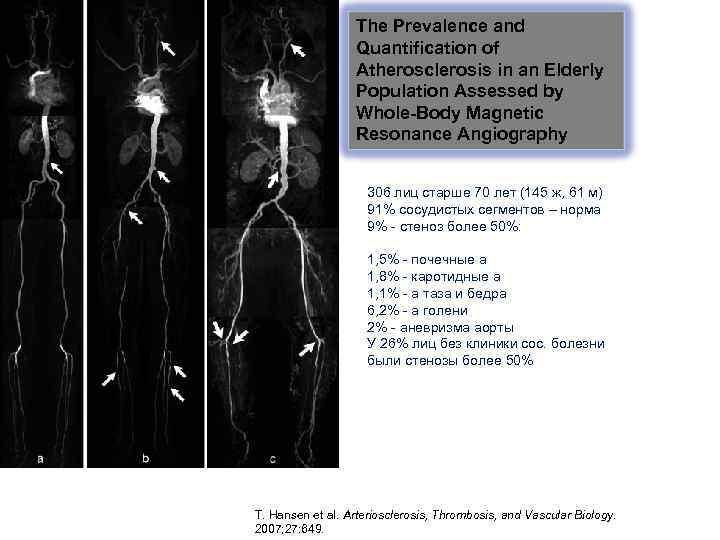

The Prevalence and Quantification of Atherosclerosis in an Elderly Population Assessed by Whole-Body Magnetic Resonance Angiography 306 лиц старше 70 лет (145 ж, 61 м) 91% сосудистых сегментов – норма 9% - стеноз более 50%: 1, 5% - почечные а 1, 8% - каротидные а 1, 1% - а таза и бедра 6, 2% - а голени 2% - аневризма аорты У 26% лиц без клиники сос. болезни были стенозы более 50% T. Hansen et al. Arteriosclerosis, Thrombosis, and Vascular Biology. 2007; 27: 649.

The Prevalence and Quantification of Atherosclerosis in an Elderly Population Assessed by Whole-Body Magnetic Resonance Angiography 306 лиц старше 70 лет (145 ж, 61 м) 91% сосудистых сегментов – норма 9% - стеноз более 50%: 1, 5% - почечные а 1, 8% - каротидные а 1, 1% - а таза и бедра 6, 2% - а голени 2% - аневризма аорты У 26% лиц без клиники сос. болезни были стенозы более 50% T. Hansen et al. Arteriosclerosis, Thrombosis, and Vascular Biology. 2007; 27: 649.